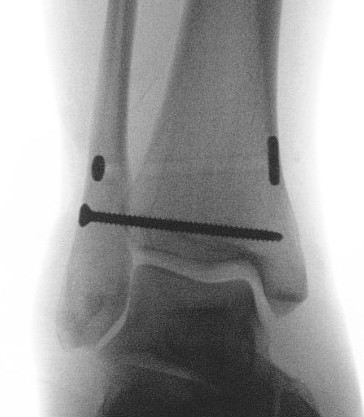

Screw fixation

Suture button fixation

Technique

Open reduction of the tibio-fibular joint

Caution in length unstable fractures (consider fixing fibula first)

One or two suture buttons

- 1.5 - 3 cm above joint line

- angle 30 degrees anterior

- need to ensure entry point centered on fibula

- risk of saphenous nerve damage of medial side

- consider medial incision to identify and protect nerve

- talus at neutral dorsiflexion when tightening